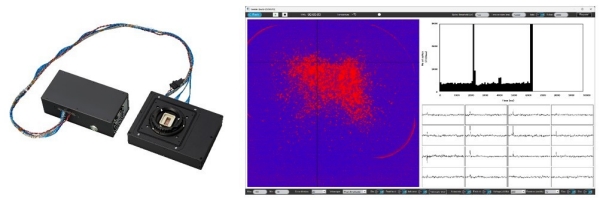

(左:MEA系统硬件,右:测量应用程序的UI示意图)

此次三家公司携手日本东北工业大学(下称“东北工大”)新开发的高密度MEA系统,可基于细胞电活动数据,在单细胞水平上比对和监测病态细胞和健康细胞的差异以及细胞对化合物的反应。具体而言,该系统通过整合索尼正在开发的高密度CMOS-MEA与SCREEN集团的细胞电活动测量技术,利用高密度排列的微电极检测细胞外电位,并输出图像数据。这使得用户能够在观测细胞放电*2的同时,精准测量与记录细胞反应。此外,该系统还集成了在索尼和东北工大的联合研究成果所构建的基础框架,搭载由VitroVo专为化合物评估优化的算法,以及具备友好操作界面的数据分析应用程序。由此,细胞放电频率等分析结果可基于电位与图像数据实时显示。该系统的测量与分析功能不仅能获取比传统MEA系统更高密度的细胞活动数据,还可捕捉以往难以观测的实验现象。

・ CMOS-MEA是一种可以实时观测细胞电活动的设备。在传感器芯片上高密度集成了的微电极阵列(Microelectrode Array; MEA),能够捕捉细胞活动过程中的离子流入流出产生的电位变化,经信号处理后输出图像数据。用户可以通过图像直观查看药物等化合物对细胞的影响以及细胞之间的信息传递过程。

・ 索尼正在开发的CMOS-MEA通过缩小电极间距,在保持紧凑体积的前提下,实现单个芯片高密度集成约23.7万个电极。同时,依托索尼在图像传感器开发过程中积累的高速A/D转换技术和高速接口技术,本系统可以实现对大规模电极数据的同步读取。